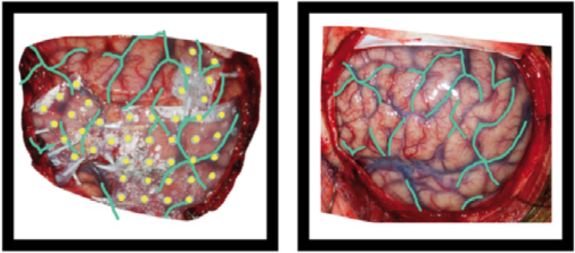

Example of the operative photo of ECoG electrodes (here is an annotated example in which electrodes and vasculature are marked, taken from Hermes et al., JNeuroMeth 2010).

Below is an example of a volume rendering of the cortical surface with a superimposed subdural electrode implantation. This map is often provided by the

EEG technician and provided to the epileptologists (for example, see Burneo JG et al. 2014. doi:10.1016/j.clineuro.2014.03.020).